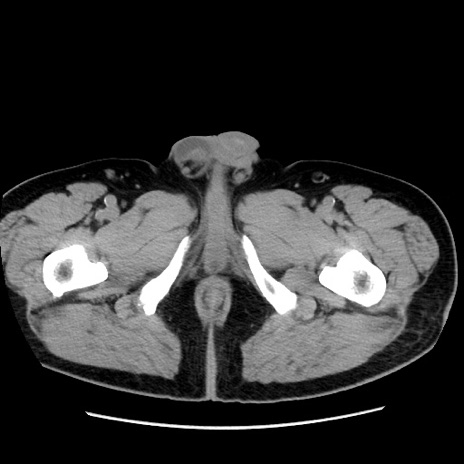

症例16(横断像)

【症例】 70歳代男性

【主訴】 腹痛、嘔吐

【現病歴】 約1ヶ月前より間欠的に腹痛と嘔吐あり、当院消化器内科を受診したところCTで多発する肝臓のLDAを指摘され、精査中であった。以降は消化器症状は安定していたが、2日前より嘔気と腹痛があり、同日より排便・排ガスが消失した。改善認めず、 本日、救急外来を受診した。

【既往歴】 大腸ポリープ切除後。

【身体所見】意識清明・会話良好、BT 36.3℃、BP 127/80mmHg、 P 80bpm、腹部:膨満あり、平坦・軟、上腹部正中および下腹部正中に圧痛あり、反跳痛なし、筋性防御なし。

【データ】WBC 7200、CRP 0.77